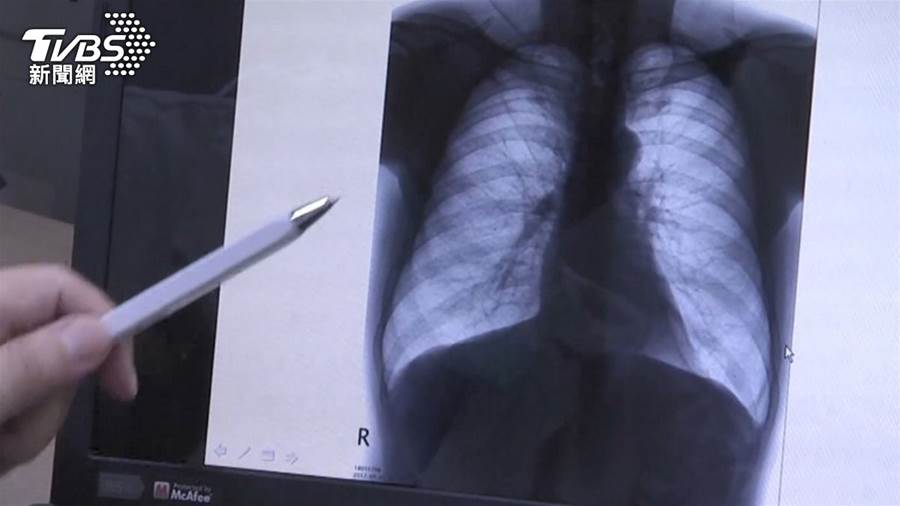

《好小子》男星顏正國肺腺癌病逝,年僅50歲。長安醫院發文指出,肺癌為近幾年來國人癌癥死因首位,其中以肺腺癌最常見,初期癥狀不明顯,常被誤認為感冒,超過7成患者確診時已是末期。

據衛福部統計,2024年全台因癌癥死亡人數為5萬4032人,有著「癌王」之稱的肺癌不僅致死率超高,前期也幾乎沒有癥狀,往往發現後為時已晚,究竟該如何嚴防,出現哪些癥狀就要注意?台中市亞大附醫胸腔內科癌癥負責醫師戴芳銓說明,唯有早期發現、早期治療,才能大大地提高存活率和生活品質,若出現異常咳嗽、常常感到很喘等呼吸道癥狀,就得特別留意。

戴芳銓解釋,在一般健康的人體內,正常的細胞組織會經歷逐漸生長,再到慢慢凋零的過程,只是肺癌細胞腫瘤會「無限制增長」,因此影響到肺部呼吸,再蔓延到血管,將身體營養全部吃掉。